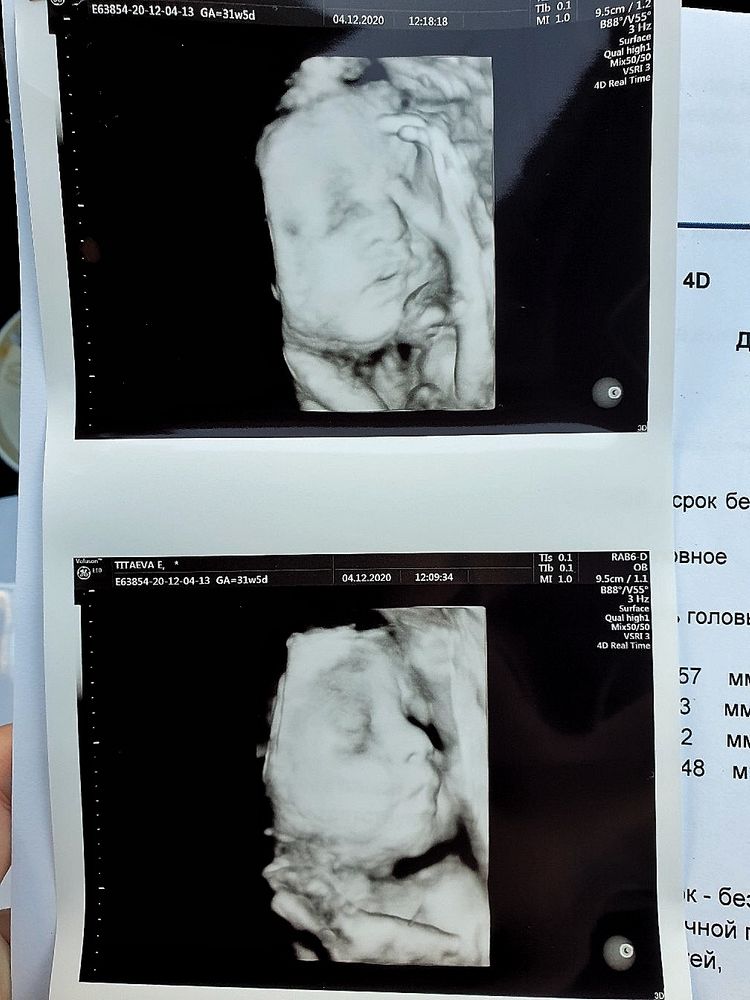

В 31+5 делала, дочка по размерам была на 30+2. Смотрю вы из Н.Новогода, советую клинику тонусМама, врач Кольцова С.В Изображение